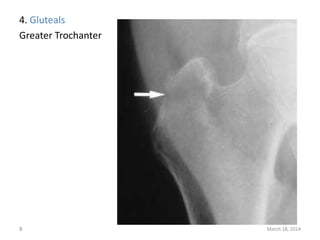

The document lists 10 common sites of avulsion fractures caused by the tearing away of tendons or ligaments from bone. It identifies the specific muscles or tendons that can cause avulsion fractures at the iliac crest, ischial tuberosity, greater trochanter, lesser trochanter, posterior calcaneus, olecranon process, superior patella, inferior patella, and tibial tuberosity.